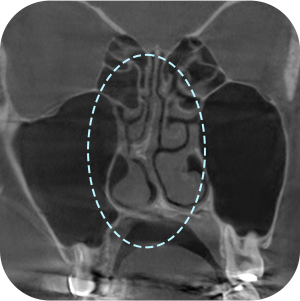

以前、手術の 保形物情報確認

鼻中隔湾曲症など 機能的問題確認

現在の保形物の 位置確認

鼻のCT撮影、どうしても必要ですか?

A再手術ですので、もっと精密に診断する必要があります。

内部の機能的な問題を正確に診断することで

安全な手術が可能となります。

鼻再手術は徹底した分析が重要です。

3D-CTを通じて正確な分析が

できるから! - 03